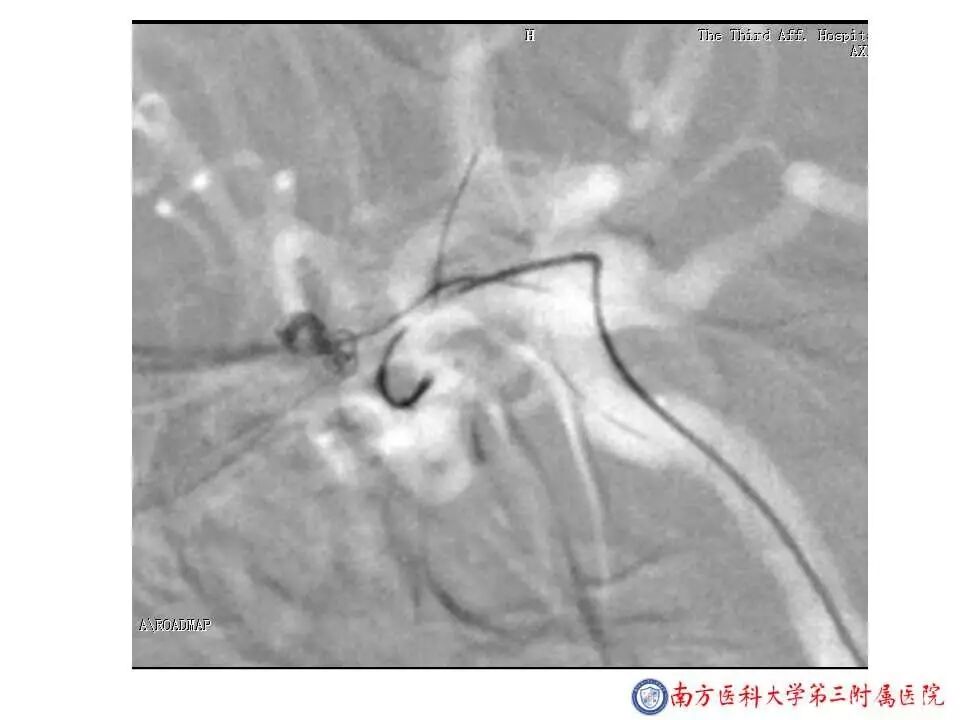

今天为大家分享的是“强生医疗CNV-神经介入专栏”第二十五期,由南方医科大学第三附属医院神经外科主任黄理金教授带来的“Enterprise支架辅助栓塞动脉瘤的优势”精彩讲课视频及PPT,欢迎观看。文章仅代表作者个人观点,如有不同见解,欢迎同道斧正!